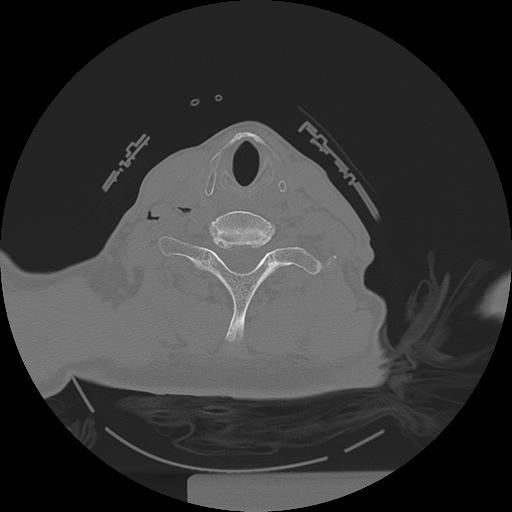

11 HUESO,,Axial,2.0,HUESO,,